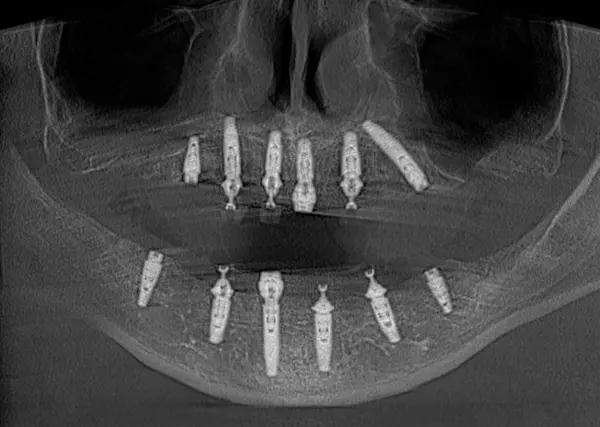

Сканы КТ имплантации зубов, 2026-04-18

Скан КТ, 2026-04-18

Сканы КТ имплантации зубов, 2026-04-18

Скан КТ имплантации зубов, 2026-04-17

Сканы КТ имплантации зубов, 2026-04-18

KT: имплантация зубов DentalKnysh, 2025-01-03, сканы

KT: имплантация зубов DentalKnysh, 2025-01-03, сканы

KT: имплантация зубов DentalKnysh, 2025-01-03, сканы

КТ имплантации зубов в DentalKnysh (10 имплантов), 2023-11-03

С 2023-09-05 по 2023-09-09 сканы КТ от 6 до 12 имплантов в DentalKnysh (4 фото):

Синуслифтинг и имплантация зубов, 6 имплантов, all-on-6, КТ скан 1, 2023-08-31

Фото отчет Имплантация зубов, 6 имплантов, КТ скан 3, 2023-08-31

Фото отчет Имплантация зубов, 8 имплантов, all-on-4, КТ скан 1, 2023-08-31